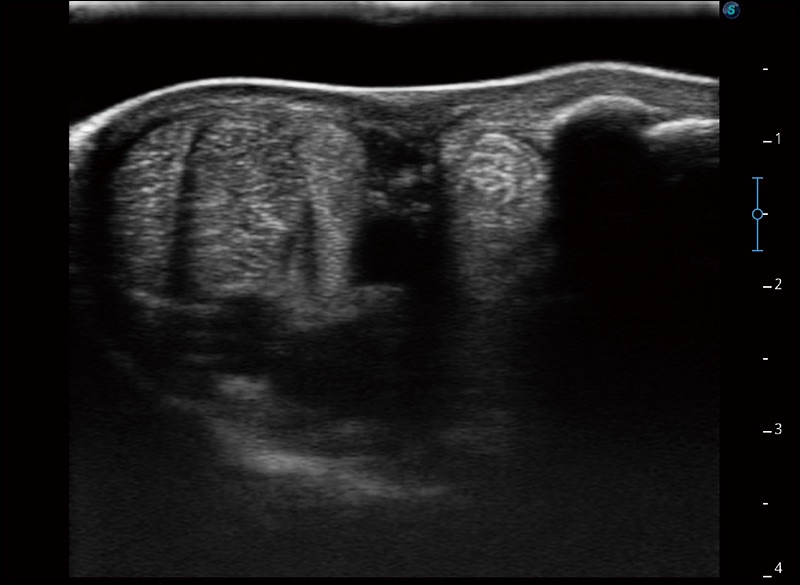

空间复合成像

优化不同角度的图像